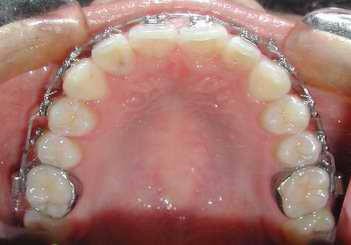

2、矫正拔牙。牙齿矫正时有些方案需要拔牙矫正,这时候拔牙是为了为即将矫正的牙齿预留出足够的空间用来排齐牙齿,如果拒绝拔牙可能会影响矫正效果,比如矫正后会面临嘴凸的现象。